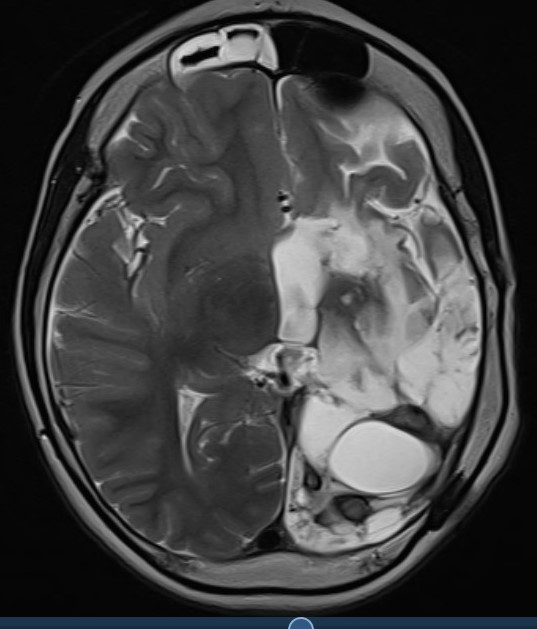

The following images accompany comments at the foot of this post.